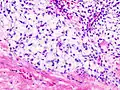

Histopathologic image of chondrosarcoma of the chest wall. Surgical resection of recurrent mass. H & E stain.